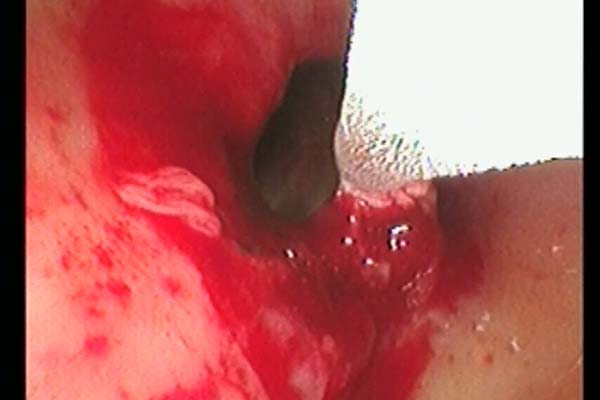

手术中,胸外科团队采用多技术联合操作策略:首先通过常规电子支气管镜完成病变探查与定位,随后置入硬支气管镜建立稳定操作通道,保障术中通气安全。针对气道内增生组织,团队交替使用氩气刀进行精准切除,并应用冷冻治疗仪对残余病灶进行消融与止血。最后在硬镜支撑与细支气管镜引导下,完整取出原有气管支架,未对气道黏膜造成附加损伤。

图3 术中冷冻治疗

图4气道肿物清除术后图